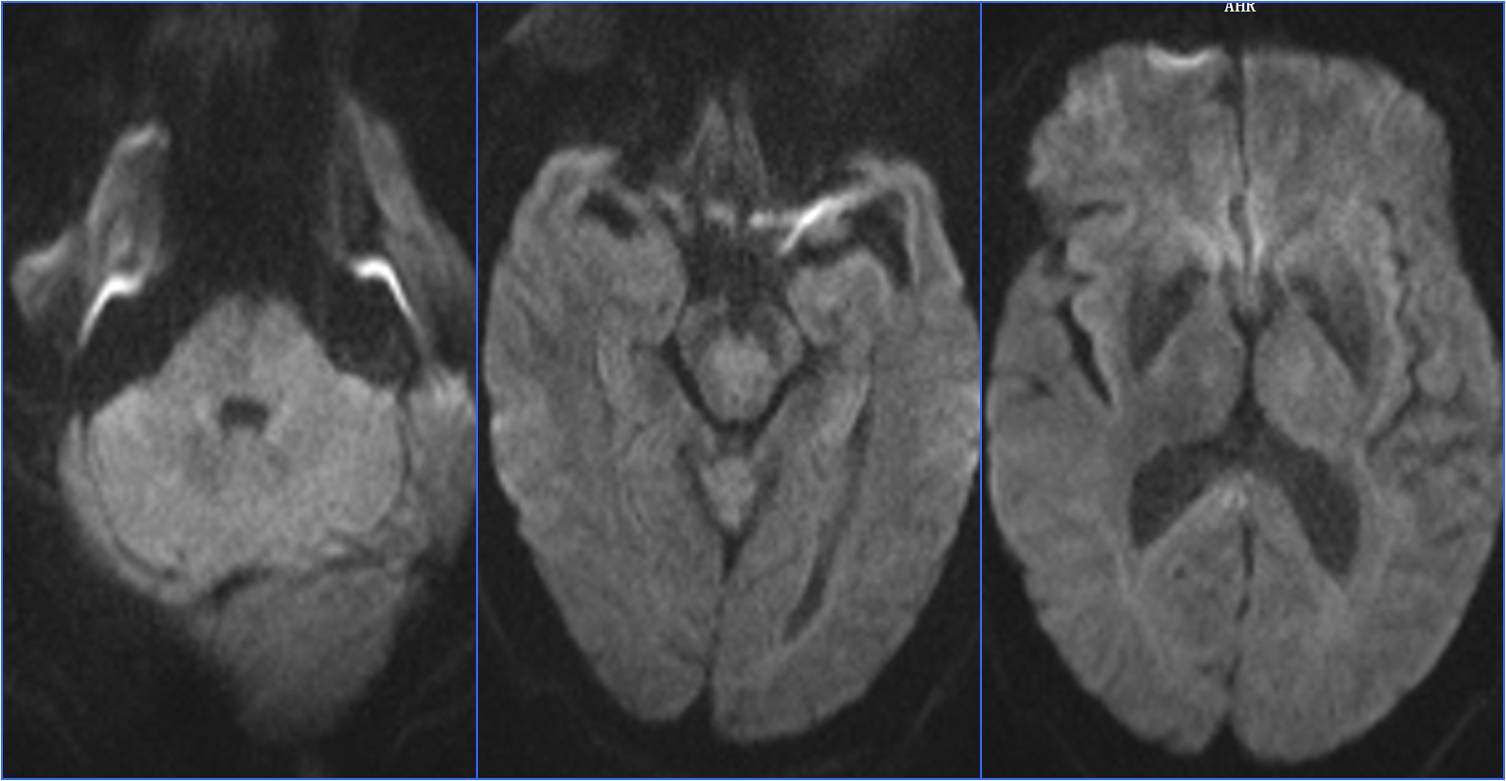

》昏迷后行头MRA检查。

▼7:22头CT

▼8:36头MRA

▼于基底动脉远端及双侧大脑后动脉,分次给予阿替普酶共计5mg。

▼溶栓后MRI